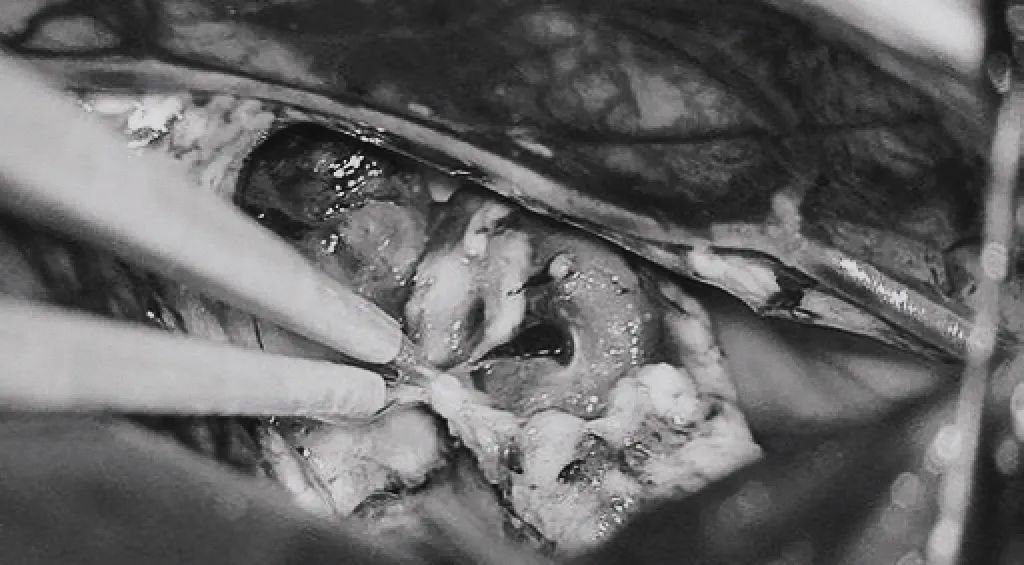

▼(h)引流静脉进入ICV处电凝。完全切除AVM。